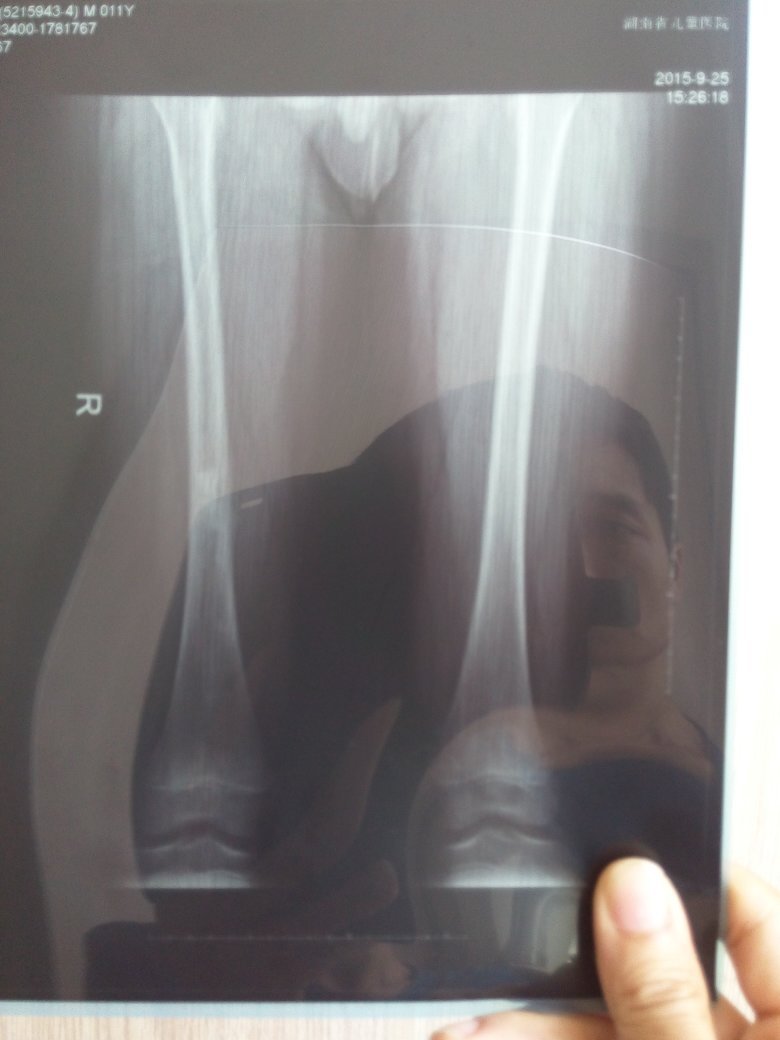

小孩因为髋关节滑膜炎住院8天,髋部疼痛有反复。遂出院去省儿医门诊,拍股骨时发现中段有阴影。又返回地级最大医院住院,说要手术。那我想请问做核磁共振能知道是哪种骨肿瘤吗?良性还是恶性?小孩现在快2天没疼了,是不是可以保守治疗?过2个月再复查